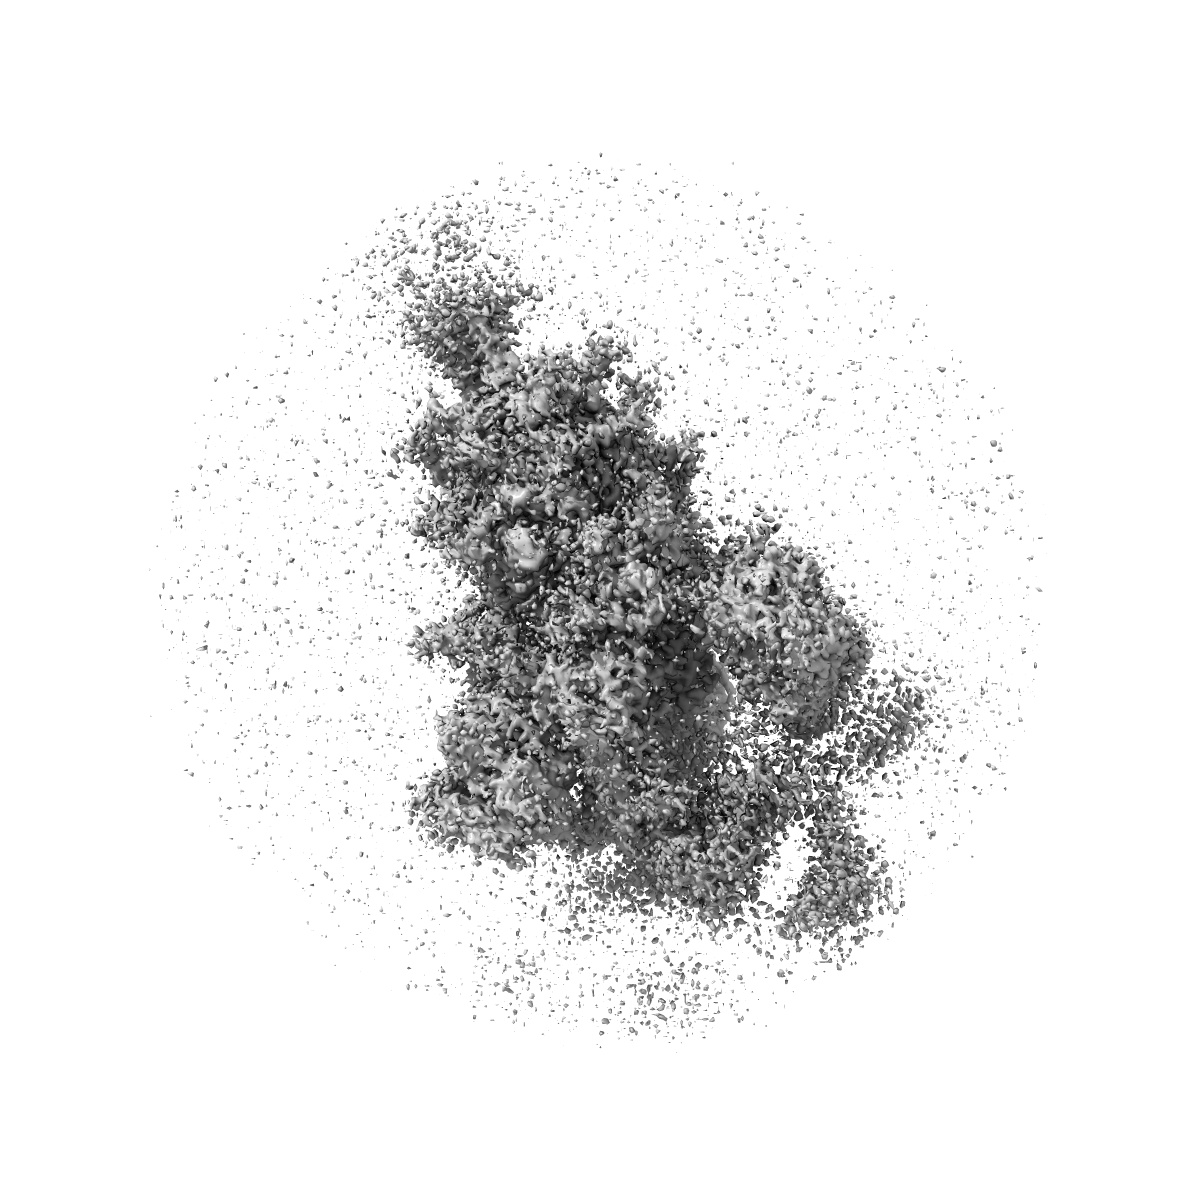

S protein of Delta variant in complex with ZWC6

Sample: S protein of Delta variant in complex with ZWC6